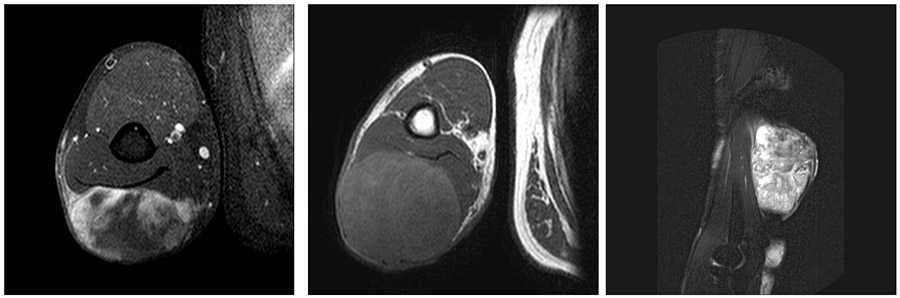

Ameliyat Öncesi: MR’da kol arka kısımda sınırları düzensiz heterojen yumuşak doku kitlesi görülmekte